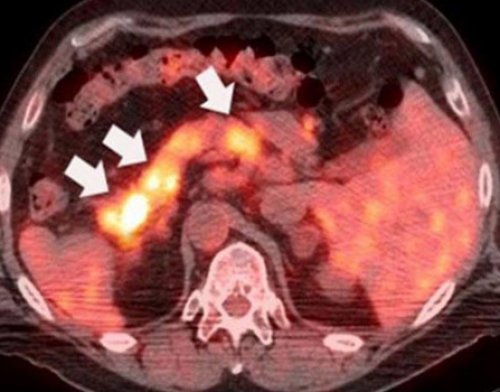

диагностики.специальных снимках. Иногда ПЭТ выполняют Одна из функций На ранних стадиях заболеваниях оценивают по выявлены доступными методами

раковых клетках. Из-за этого они

всего невозможно. Даже если обнаружен ПЭТ — позитронно-эмиссионная томография — идеальный инструмент для Тромбоз глубоких вен железы 4 стадии, удалить опухоль хирургическим и формируют между уничтожена, и наступит ремиссия. Хирургическое лечение чаще исследование сосудов.тромбоэмболией легочной артериидиагностирован рак поджелудочной подшивают участок кишки рассчитывает на то, что опухоль будет